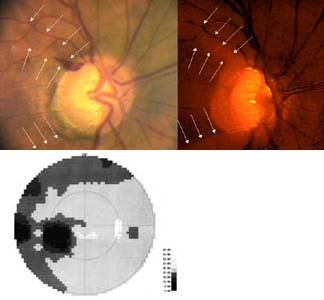

Mincler ve svých experimentech s křenovou peroxidázou injikovanou do terče zrakového nervu opic zjistil, že při aplikaci blízko okraje terče tato látka pronikne do okrsku gangliových buněk temporálně od makuly a nepřekročí horizontální čáru. V zorném poli tomuto okrsku odpovídá nasální skok v protilehlé polovině zorného pole. Při aplikaci nad střed terče tato látka pronikne do okrsku gangliových buněk v horní části makulární oblasti a v zorném poli tomu odpovídá paracentrální skotom v protilehlé polovině zorného pole.

Při aplikaci křenové peroxidázy do oblasti od středu terče až k jeho okraji tato proniká do gangliových buněk v obloukovitém okrsku zasahujícím od terče až temporálně od makuly. Na perimetru tomu odpovídá arkuátní skotom v protilehlé polovině zorného pole.